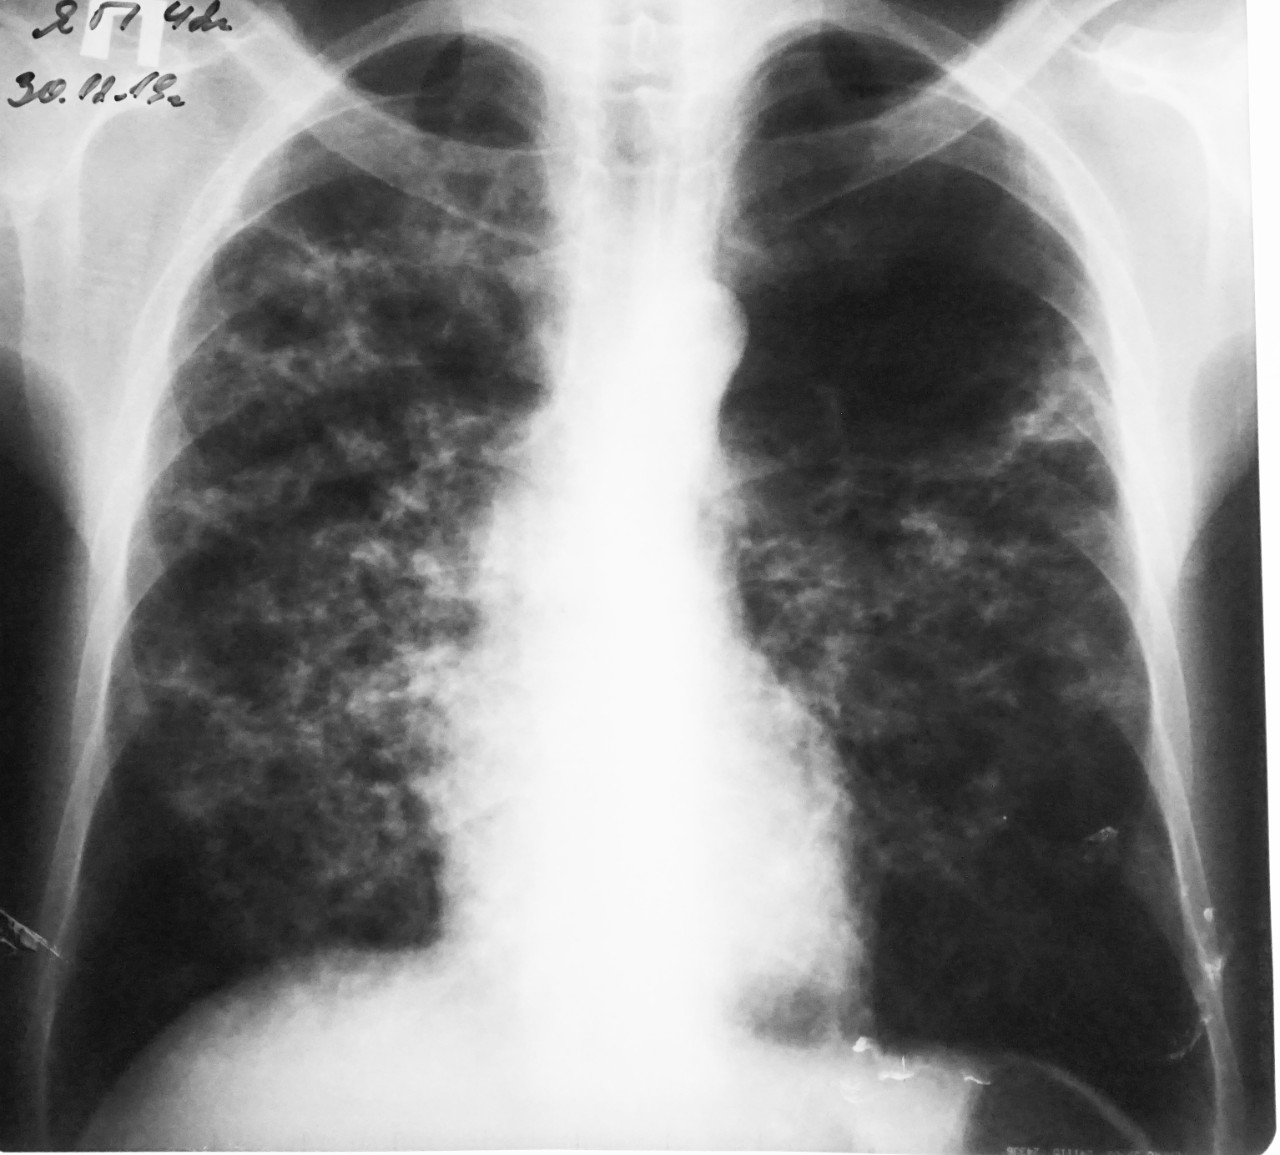

Снимок легких при туберкулезе является важным методом диагностики этого заболевания. На рентгеновских снимках можно увидеть изменения в легких, которые свойственны туберкулезу.

Диссеминированный туберкулез на рентгенограмме

Милиарный туберкулез рентген

Диссеминированный туберкулез рентген

Милиарный туберкулез рентген

Милиарный туберкулез рентген

Острый диссеминированный туберкулёз лёгких рентген

Милиарный туберкулез рентген

Милиарный туберкулез рентген

Диссеминированный туберкулёз лёгких рентген

Милиарный диссеминированный туберкулез

В данной статье представлены многочисленные фотографии снимков легких при туберкулезе, чтобы помочь вам понять, как выглядят изменения легких на рентгеновских снимках при этом заболевании.